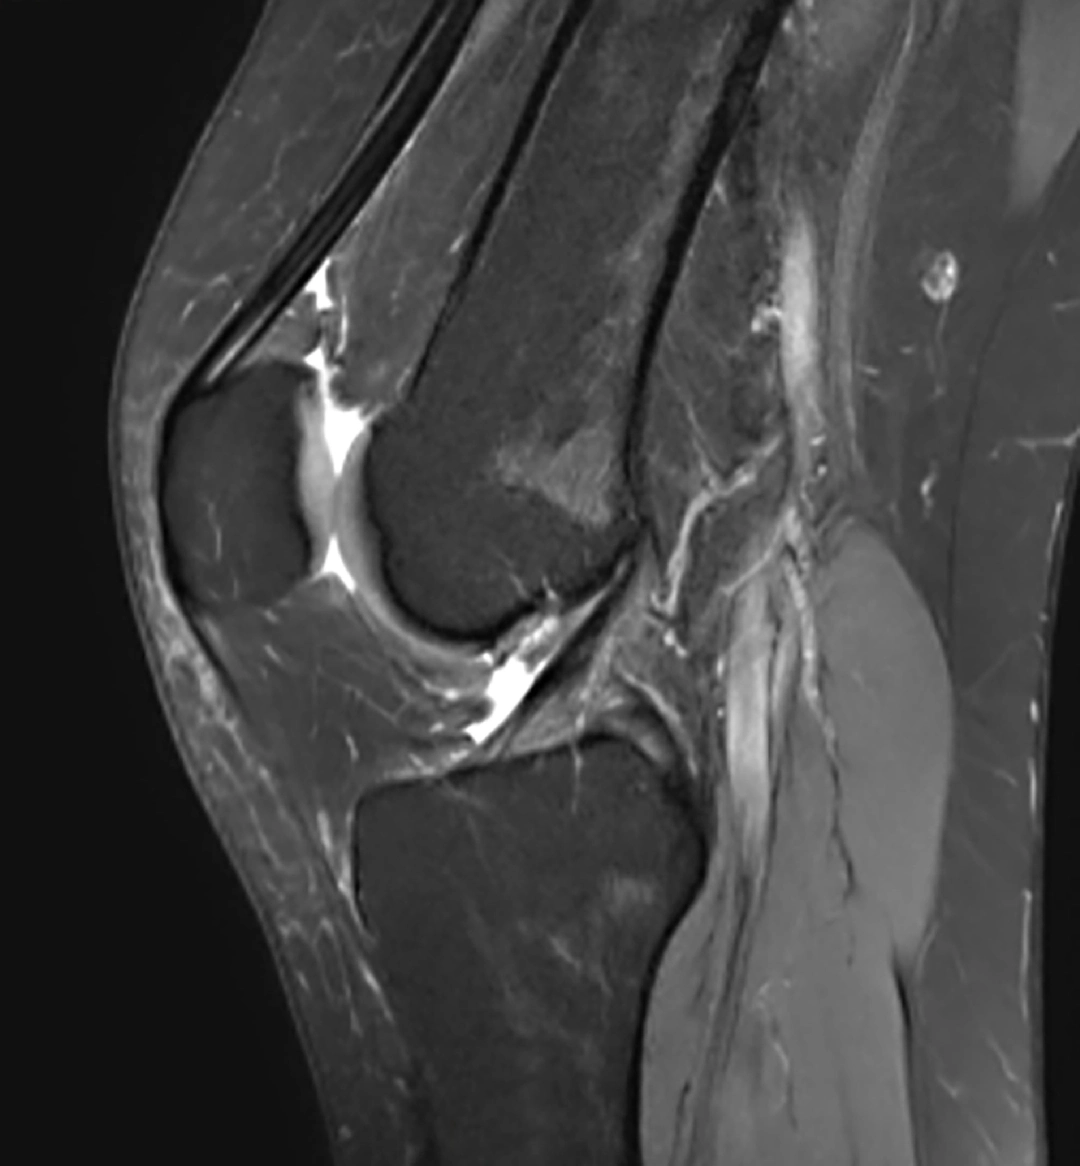

La RM 3T permite obtener imágenes de altísima resolución, con un nivel de detalle superior al de los equipos convencionales. Gracias a ello, se facilita la correcta valoración de estructuras complejas como:

Cartílago

Meniscos

Ligamentos

Tejidos blandos

Esta capacidad de detalle resulta fundamental para detectar lesiones con mayor exactitud y reducir el margen de error diagnóstico.

Estudio de rodilla mediante RM 3 Teslas de VOT, con alta definición anatómica y excelente contraste tisular para una valoración precisa de estructuras osteoarticulares y partes blandas.